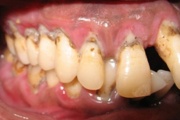

Agressiivse parodontiidi kahjustused rasedal naispatsiendil